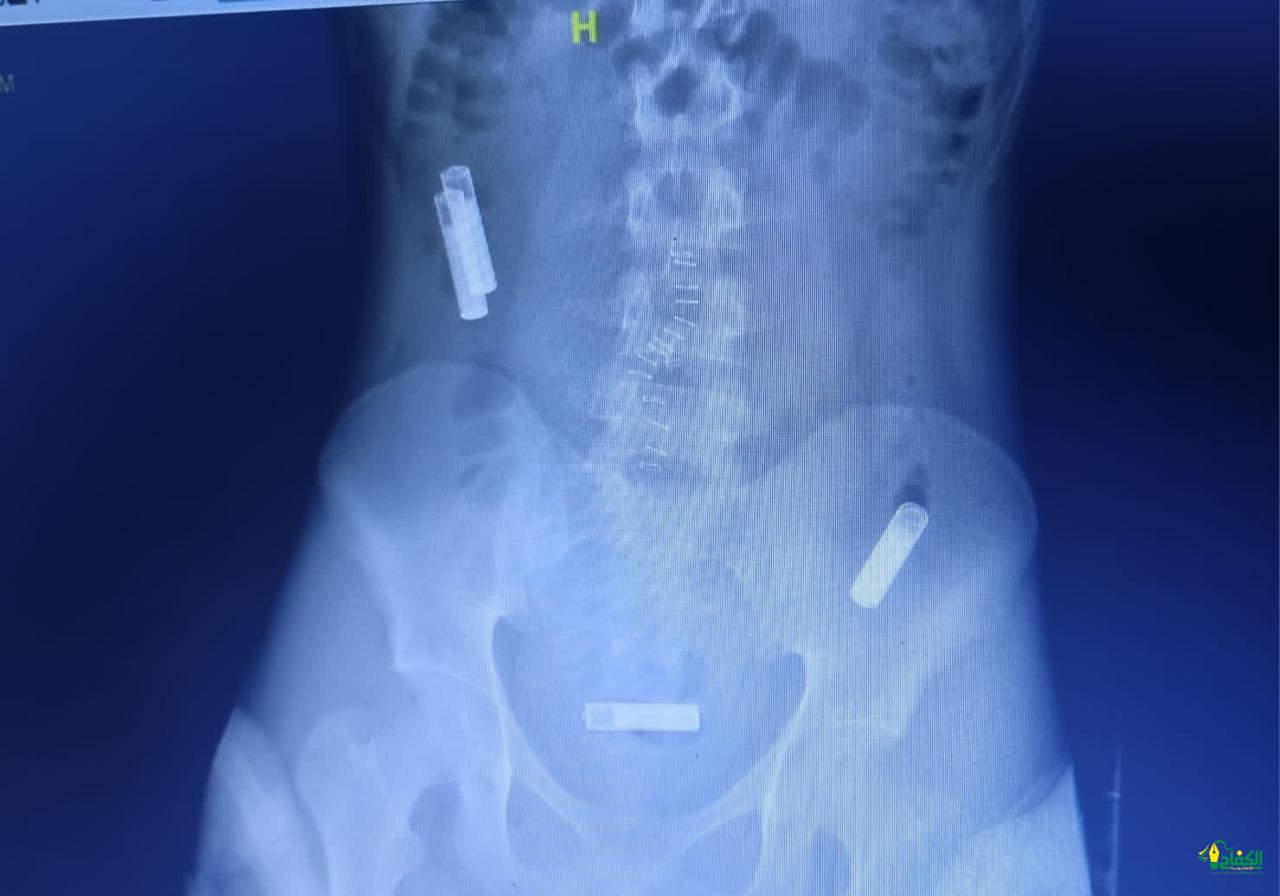

وأوضح تجمع مكة المكرمة الصحي، أن المريض حضر الى قسم الطواري والحوادث وهو يشتكي من آلم بالمعدة مع غثيان وقيء وبعد عمل الفحوصات الطبية والأشعة المقطعية اتضح وجود 3 بطاريات داخل بطن المريض وعلى الفور تم عمل عملية المنظار التي استغرقت 35 دقيقه واستخراج البطاريات من الأمعاء الدقيقة وقولون المريض.